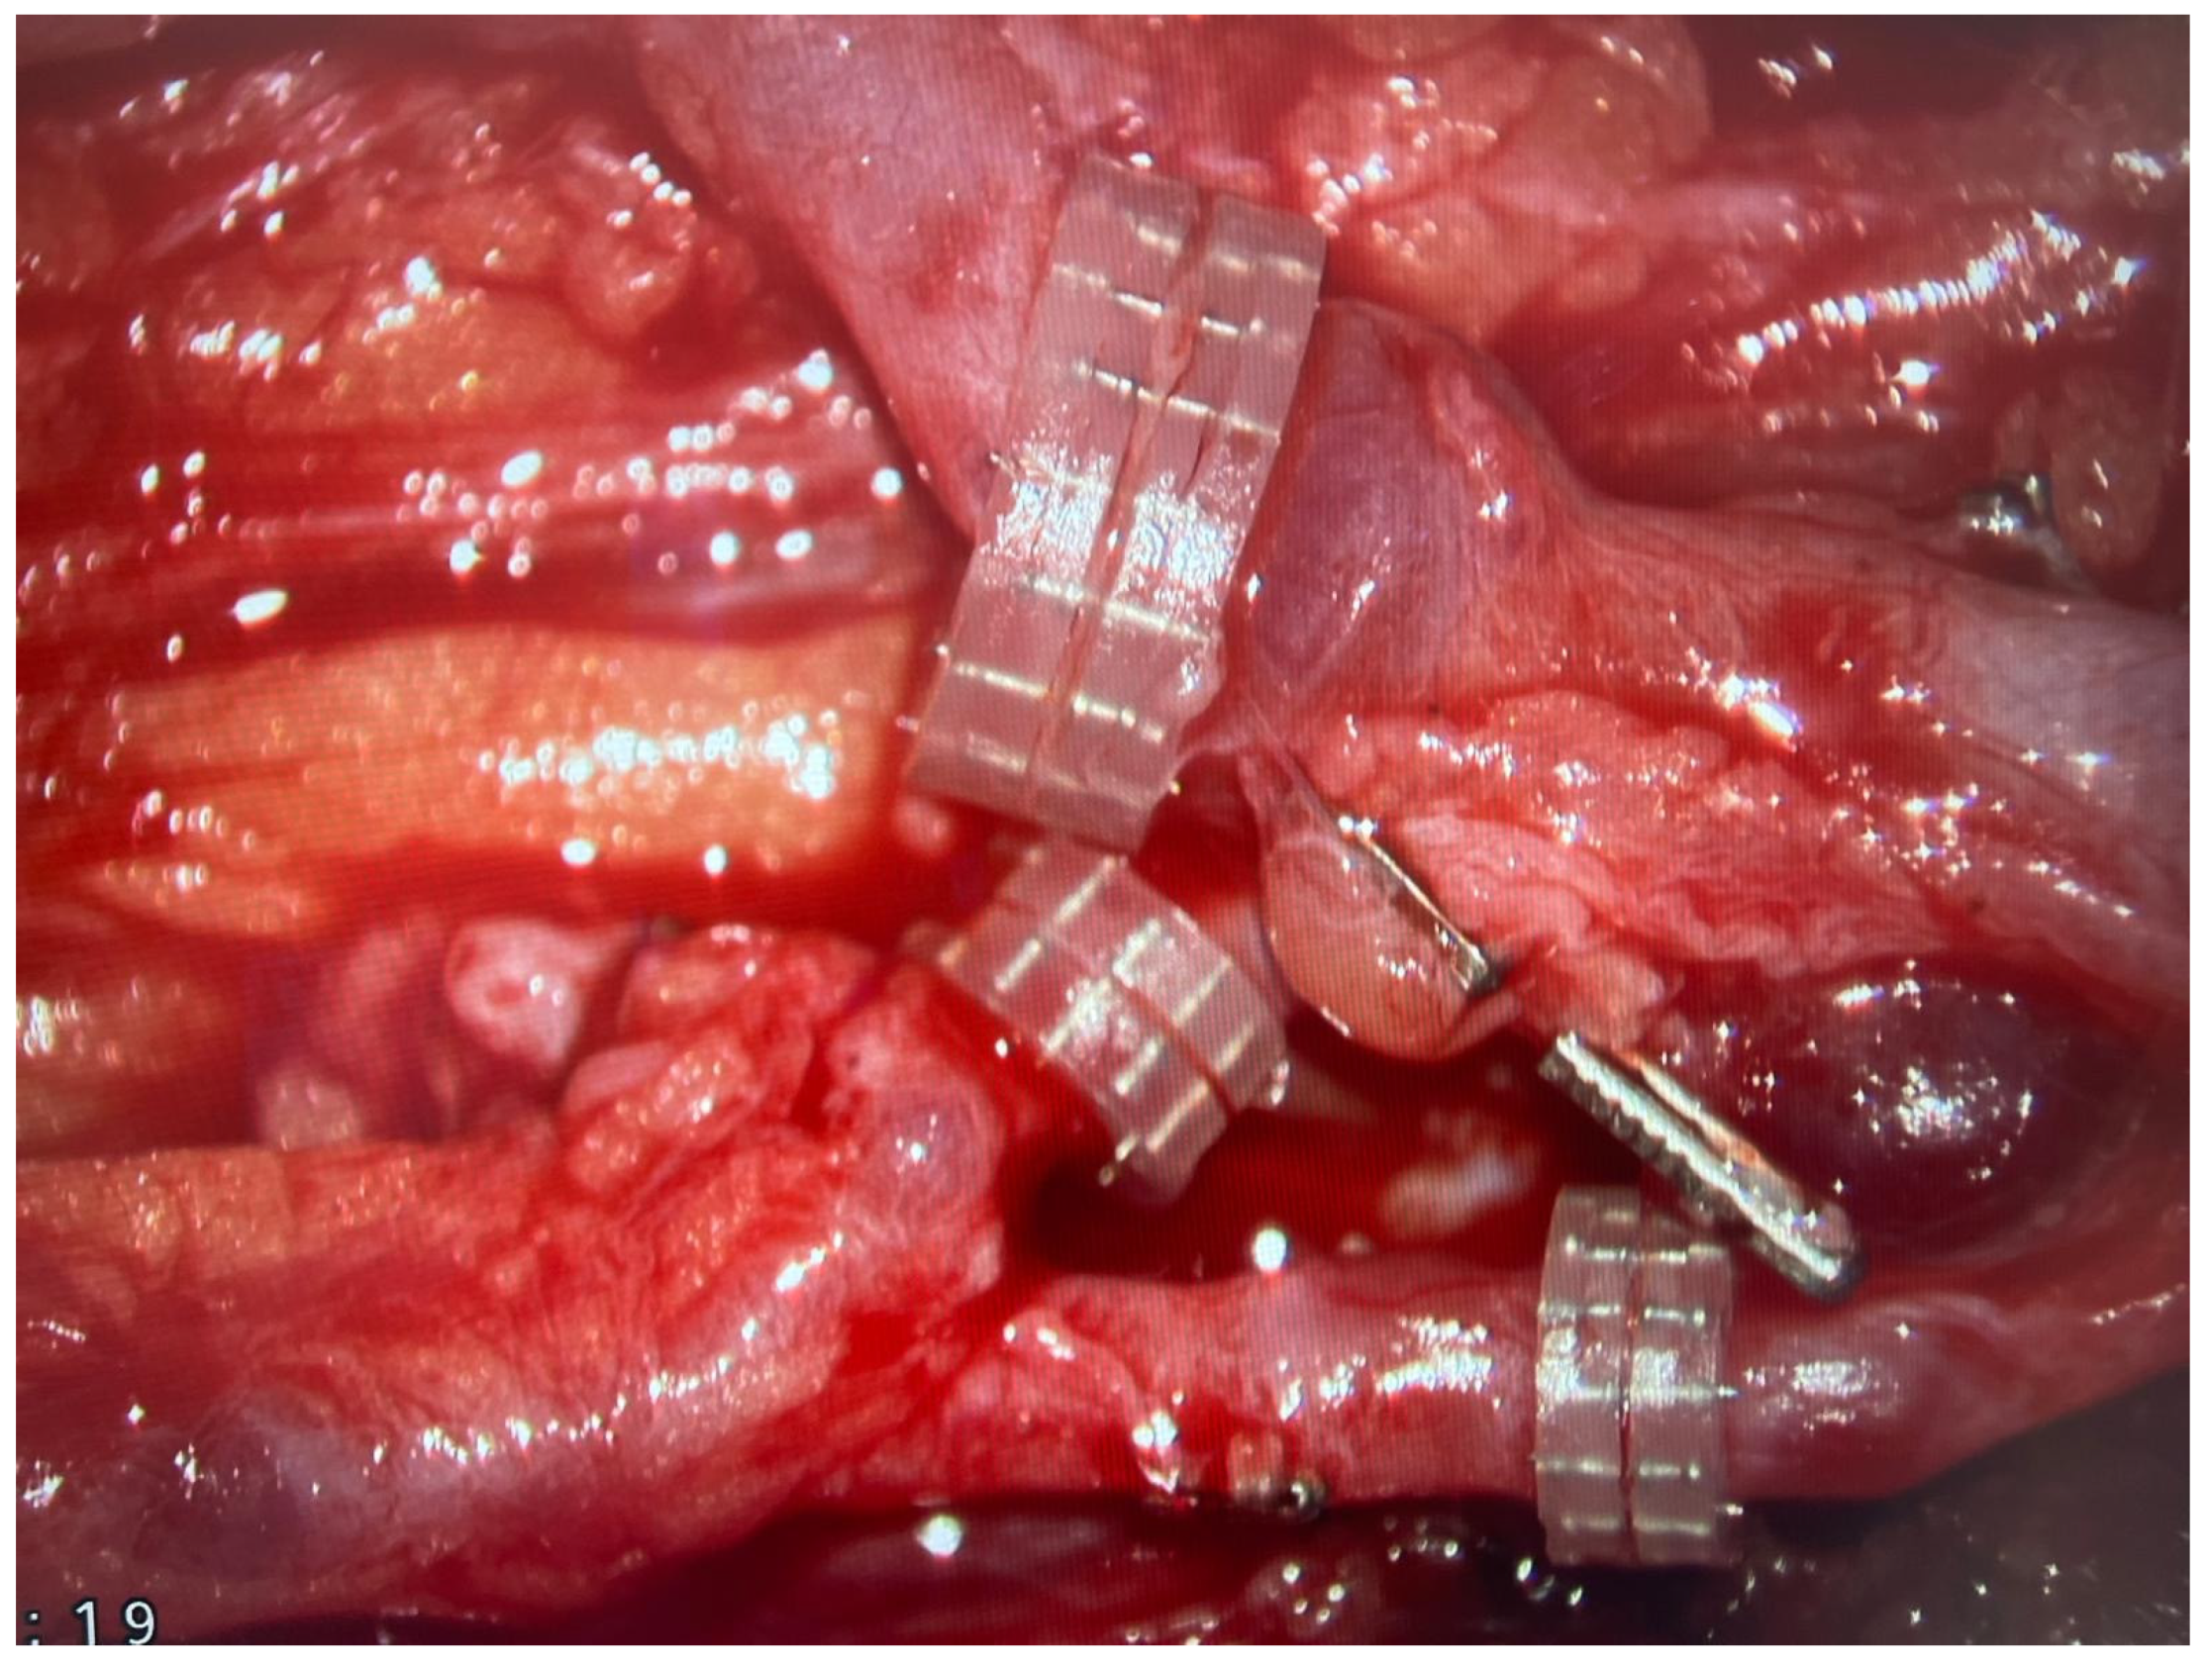

In the vast majority, the microanastomoses were performed between the FFF pedicle and branches of radial vessels. In every case, there was one arterial anastomosis and two veins connected. Veins from the FFF pedicle were anastomosed to both the superficial and deep veins of the upper limb (most commonly the cephalic or basilic vein). All venous microanastomoses were carried out using the microvascular coupler (Synovis Micro Companies Alliance, Birmingham, AL, USA). The average size of the coupler used was 3.0 mm (range 2–4 mm). (Figure 5).

In reconstructive microsurgery, the biggest perioperative threat requiring immediate surgical intervention and frequently leading to total or partial tissue necrosis of the free flap is venous insufficiency [30]. To avoid this problem, in patients treated at our department, in order to mitigate the risk of the most common cause of flap perfusion impairment, two microsurgical veins from the FFF pedicle were anastomosed, both to the superficial and deep venous systems within the upper limb (Figure 5).

Figure 5. Three microvascular anastomoses performed with the use of coupler system are presented with the use of surgical microscope.